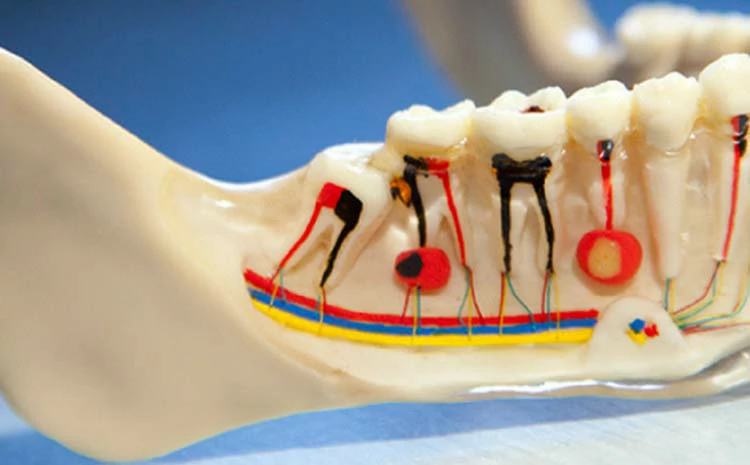

2- علاج قناة الجذر

هو الخيار المثالي لـ علاج خراج الاسنان، وفيه يتم إزالة أنسجة لب السن أو الضرس المتضرر؛ من أجل الاحتفاظ بالسن وعدم خلعه.

خلال الإجراء، يقوم الطبيب بإعطاء المريض حقنة مخدرة موضعية في اللثة؛ لتخدير أجزاء الفك والفم المتضررة من الخراج، بعد ذلك يقوم الطبيب بإزالة اللب المصاب، ويقوم بتنعيم الجزء الداخلي من قنوات اللب، ثم يعمل على حشو السن بمادة حشو معينة.

بعد مرور بضعة أشهر، يخضع المريض لفحص بالأشعة السينية وفحص للأسنان؛ للتأكد من أن موقع الخراج قد تعافى تمامًا، ويعتبر هذا الخيار من خيارات العلاج التي يفكر بها الطبيب إذا استمر المريض بالشعور بالألم بعد حل مشكلة الخراج.